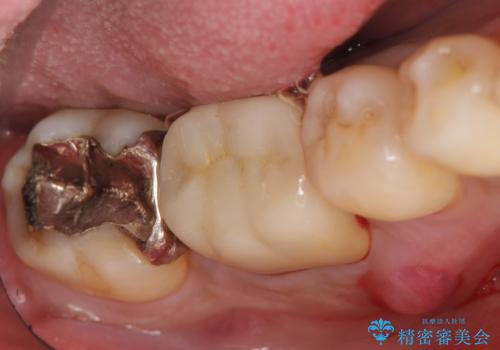

- 数年前から歯茎から膿が出る、治療してもよくならないので診て欲しいといらっしゃった方の症例です。

再根管治療を行い膿の出口の消失及び根尖病変の縮小を確認後、オールセラミッククラウンによる補綴を行いました。